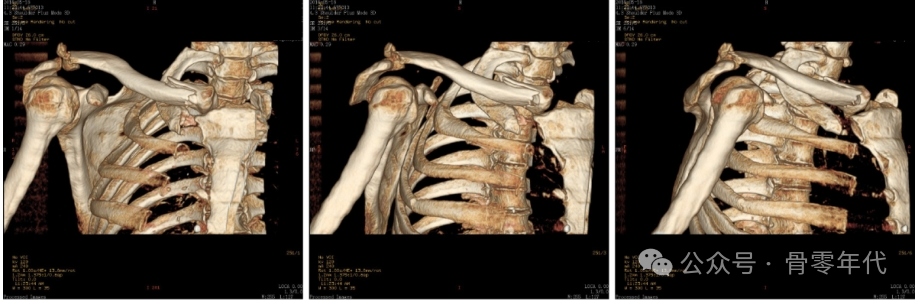

一名56岁的保安在从电动自行车上摔下,右肩疼痛来到医院就诊。在患者的标准X线片上,锁骨骨折的近端和远端均被分离。CT从不同角度显示锁骨骨折移位情况。术后骨折线、脱位均恢复。

1例锁骨远端骨折伴锁骨近端脱位患者的影像表现。钢板内固定治疗双极锁骨损伤1例。利用杠杆复位锁骨两端,然后分别放置新的胸锁钢板和肩锁钢板。术后对患者进行影像检查。X线和CT图像